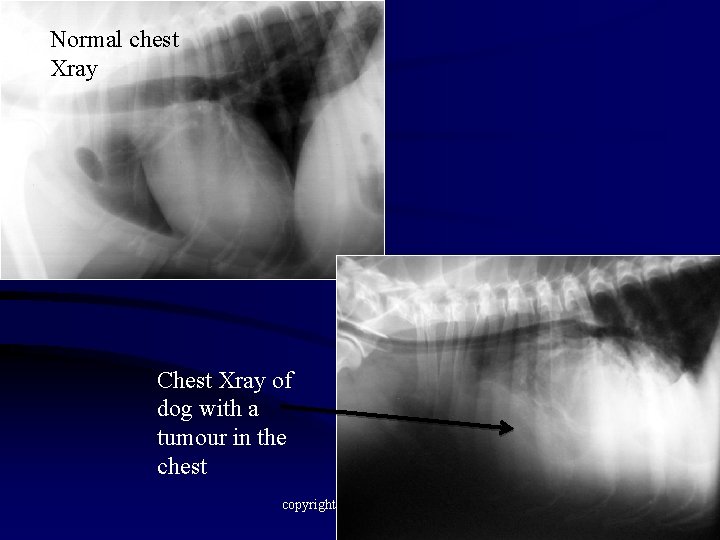

Normal chest Xray Chest Xray of dog with a tumour in the chest copyright A Hotston Moore